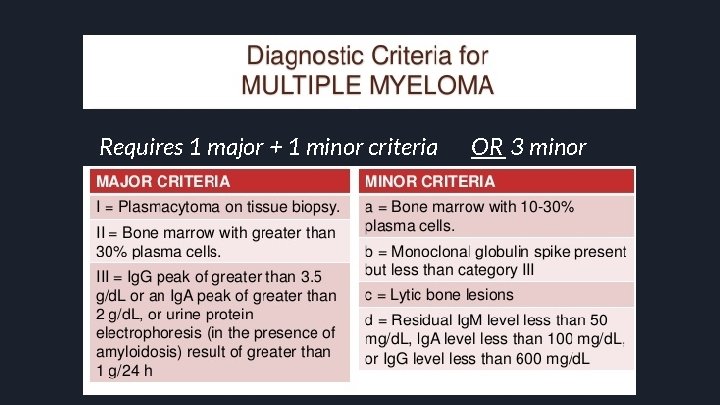

Requires 1 major + 1 minor criteria OR 3 minor

Requires 1 major + 1 minor criteria OR 3 minor criteria